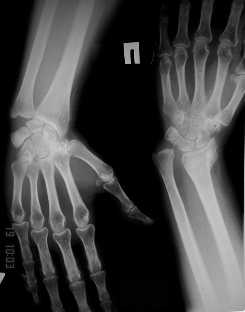

Обратилась женщина, 55 лет. Травма 3 месяца назад, лечилась по месту жительства (Рис.1). Косорукость, боли, ограничение движений. Досняли - рис.2-6. Хотелось-бы услышать мнения  об объеме операции.

Имя     : 2.JPG